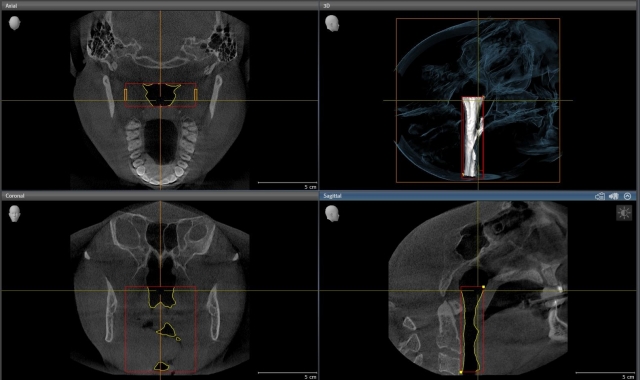

You are not a tooth-fixer; you are a facilitator of health and wellness every day in your practice, using the gifts and tools that you have. Similar to the undeniable and obvious evolution of airway into the dental field, we continue to evolve in the direction of simply helping move people toward health in a manner that’s appropriate for each patient (Figs. 4 and 5).